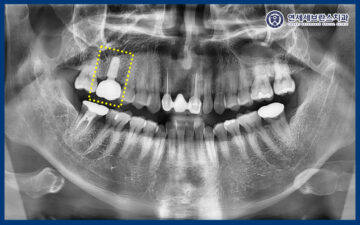

<타 치과 임플란트 통증>

위 환자분께서는 오른쪽 위가 씹을 때 아프다며

본원에 내원해 주셨는데요.

엑스레이 상 특별한 문제가 보이지 않았으며,

구강 내에서도 흔들림과 같은 문제가 없어서

일단 교합조정 후 증상을

체크해 보기로 하였습니다.

25.08.29

<식립 후 한달 체크>

그리고 임플란트는 식립 후 약 한 달간의

초기 치유 기간이 매우 중요한 시기로,

이 시기에 임플란트와 주변 골 사이의

안정적인 결합이 형성되기 때문에

세심한 경과 관찰이 필요합니다.

그래서 환자분께 내원하시도록 안내드렸고,

엑스레이 촬영을 통해

곡반정동임플란트와 주변 골이 안정적으로

잘 유지되고 있는지 확인했습니다.